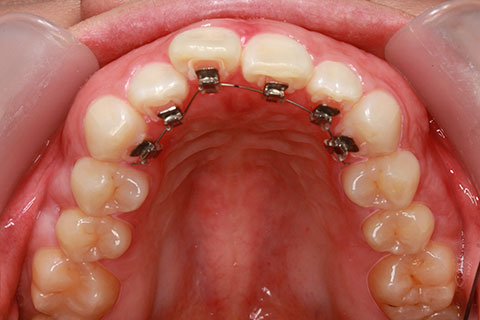

ハーフリンガル矯正2(上の歯のみ舌側矯正で治療)

治療前

治療中

治療後

- 年齢・性別

- 23歳女性

- 治療期間

- 1年6ヶ月

- 抜歯

- 上顎4番

- 治療費

- 110万円(税込み)

- 備考

- ハーフリンガル矯正

- 治療内容

- 上下前歯部凸凹の改善

- 施術の副作用(リスク)

- 裏側矯正の特性上、表側矯正と比較すると治療期間が長くかかる場合が多い。